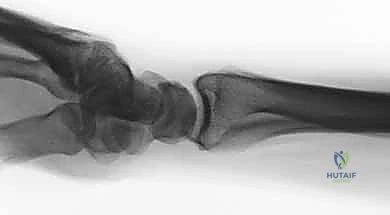

- تشوه مرئي (Deformity): في حالات الانزياح الكبير، قد يبدو الرسغ معوجاً أو منحنياً بشكل غير طبيعي. يُعرف التشوه الكلاسيكي باسم "تشوه شوكة العشاء" (Dinner Fork Deformity)، حيث ينزاح الرسغ للخلف.